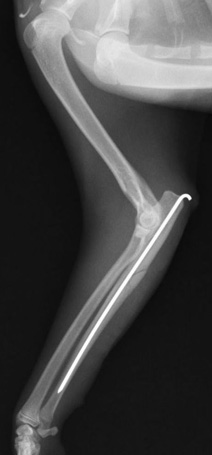

後肢の骨折:脛骨腓骨骨折

骨折時

手術後

手術写真①

完全に骨折して、骨がずれています。

手術写真②

正常な位置に骨を整復します。

手術写真③

プレートとスクリューを用いて固定します。